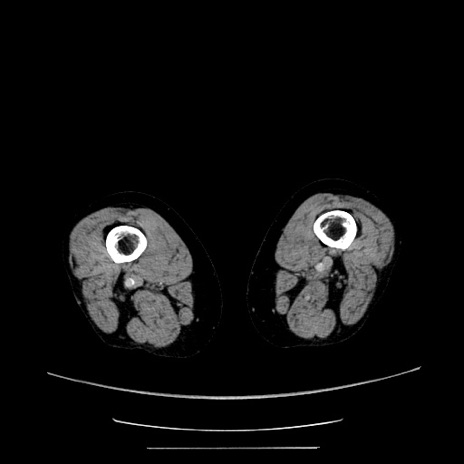

症例5(横断像)

【症例】70歳代女性

【主訴】お腹が張る

【現病歴】1週間くらい前から腹部膨満の自覚あり。昨日夜から増悪したため、本日救急外来受診。

【身体所見】意識清明、BT 36.5℃、BP 165/106mmHg、HR 80bpm、SpO2 98%、腹部:膨満、軟、自発痛・圧痛なし、触診にて不快感あり、腸蠕動音:減弱

【データ】WBC 12600、CRP 1.04